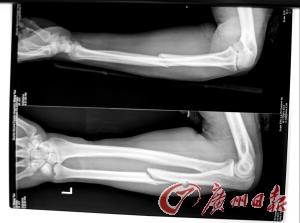

拍片显示环卫工手臂骨折。

事后,肇事者张某自行驾车离去。李生云的同事协助李生云报警。经珠海市第二人民医院医生诊治,确诊为“左尺骨中段骨折、全身多处软组织挫伤”,由于伤势严重,必须进行手术。

据主管医生徐医生介绍:由于骨折,必须进行手术治疗,手术中需植入钢板固定。待手术后,根据恢复情况,再决定何时取出钢板,一般在1年后。手术后3个月内,将无法从事现工作,何时能工作,要待术后3个月复查结果而定。